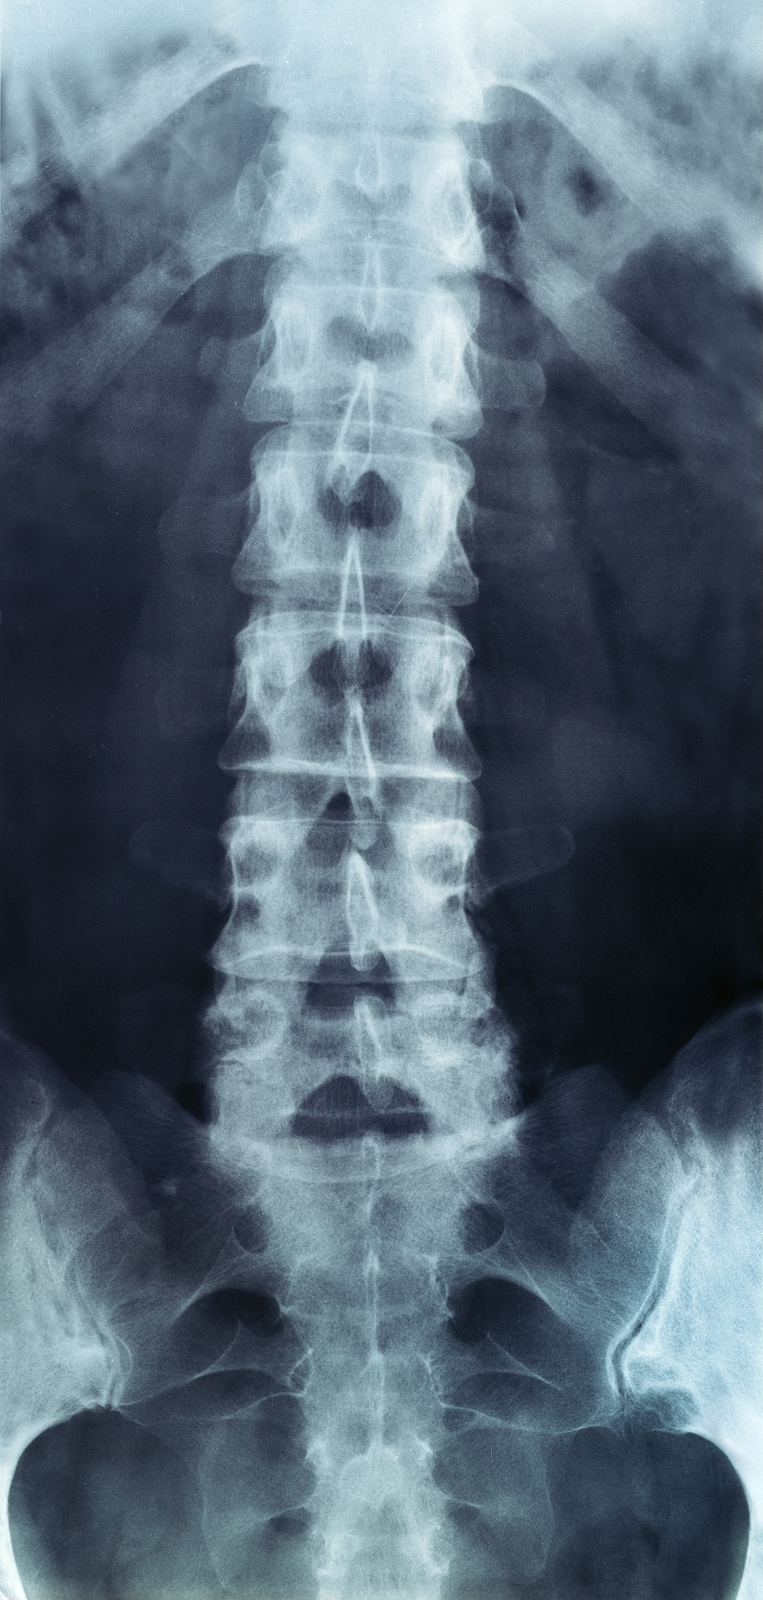

X-rays

X-rays are usually the first test ordered before any of the more specialized tests are completed. X-rays use electromagnetic radiation to show problems with bones and can also reveal problems such as fractures, infections, or bone tumors. X-rays of the spine can give your doctor information about bone alignment and can demonstrate how much degeneration has occurred in the spine. Both alignment and degeneration can affect the amount of space in the neural foramina and between the discs, which subsequently impacts the nerves in the area. This is important information your health care professional can use to establish a treatment plan.